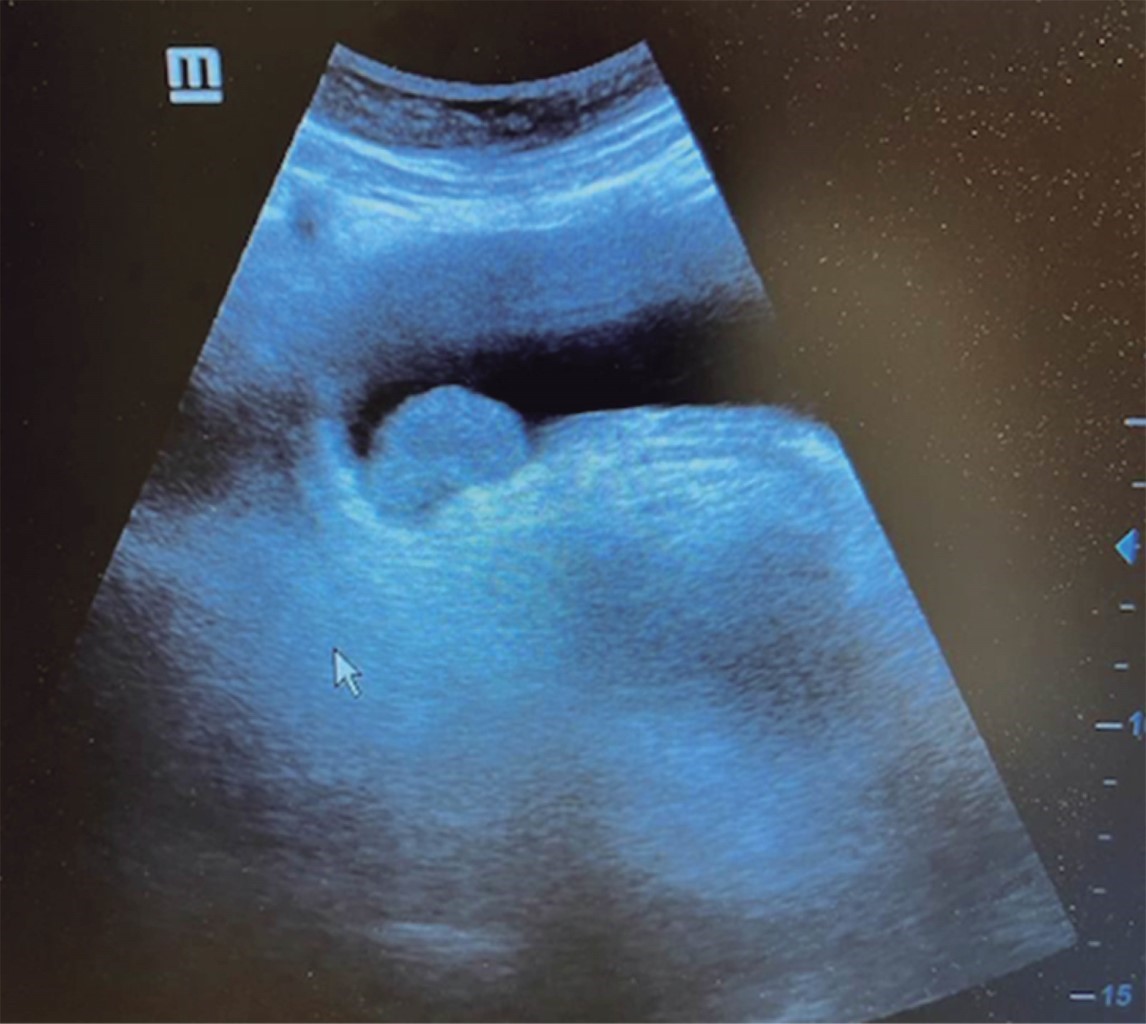

The general surgeon deals with clinical problems involving the digestive tract, the neck, the abdominal wall, and disorders of the circulatory system and the thorax. A paper published in 2008 by Lindelius,15 demonstrated that the implementation of ultrasound by the general surgeon in cases of acute abdominal pain increased diagnostic accuracy by 7.9%. In the daily consultation of the specialty, incorporating sonographic scanning to the explored area adds minutes to the clinical examination that provides data of notable value due to its objectivity and precision. The abdomen is usually the site most frequently explored by general surgeons. It is possible in a daily consultation to do the entire upper abdominal ultrasound protocol in minutes, which includes both upper quadrants and the flanks, being able to observe the liver, gallbladder and bile ducts, both kidneys, the spleen, part of the pancreas and, with the help of color Doppler, the main vessels of the region such as the inferior vena cava, abdominal aorta, portal vein, splenic vessels, and the hepatic artery. There may be limiting factors such as gastric contents, the filling level of the gallbladder, or the patient's constitution and ability to cooperate with the study. However, with daily practice, sufficient skills and refinement are acquired to achieve, with accumulated experience, images of immediate diagnostic relevance. In the training phase, contrasting our findings with information available on the web, with imaging colleagues, or surgeons already experienced in ultrasound, will allow the essential feedback and mentoring of any learning curve. Traditionally, it was considered that those organs containing a mixture of liquid and gas (intestine, stomach) are not assessable by ultrasound; the gas produces a rarefaction effect, as it does not compress the waves as a solid tissue or a liquid medium, the signals are then scattered preventing them from returning as echoes and allowing the processor to form an image congruent with the scanned organ. However, when this condition changes due to a pathological state, it is possible to identify the intestinal or gastric contents and give us a more approximate idea of what is happening in that abdomen. We can, for example, tell whether a stomach is full of liquid or whether the intestine contains solid, liquid, or gaseous residue. Today's equipment can even see the intestinal wall in detail when it is dilated. It can be distinguished when the colon is fluid-occupied at the level of the left flank as might be in amebic colitis or intestinal occlusion,16 where dilatation of the small bowel ≥ 25 mm, abnormal peristalsis, the presence of free intraperitoneal fluid and edema of the bowel wall are seen (Figure 2). In cases of acute abdominal pain, ultrasound can immediately allow differential diagnoses, such as the finding of a pyelocaliceal dilatation due to nephrolithiasis (Figure 3) or an abdominal aortic aneurysm (Figure 4). A prospective study performed in Irvine, California,17 found that the diagnostic ability of the first contact physician performing ultrasound to detect cholelithiasis has a specificity of 87% and a sensitivity of 82%, while the ultrasonography test performed by an imaging physician had a sensitivity of 83% and a specificity of 86%. In other words, by saving the patient's time, the diagnosis of cholelithiasis is feasible by adding a few minutes to the initial physical examination. In cases of appendicitis, the diagnostic method considered the gold standard is computed tomography (CT). However, it has drawbacks, such as its availability, its cost, and the risk of radiation in children and pregnant patients. In such situations, especially in children, females, or thin patients, ultrasound is a powerful tool that complements the initial clinical examination. The advantages of ultrasound over CT are its ubiquity (it is already in the emergency room), low cost, absence of radiation, and differential diagnosis with gynecologic or genitourinary causes of pain. In appendicitis, the sensitivity and specificity of CT are 99.4% and 80.0%, respectively. For ultrasound, the diagnostic sensitivity is 83% and specificity is 90%. The rate of negative appendectomy is slightly higher in the CT group than in the ultrasound group, i.e., 7.1% (3/42) (CT) compared to 4.67% (5/107) (ultrasound). It should be emphasized that ultrasound is an operator-dependent technique. Experience and quality of the equipment play an important role.18 Appendicitis has several characteristic findings, such as an edematous wall and general thickening. A noncompressible non-peristaltic tubular structure measuring more than 6 mm in diameter in the right lower quadrant is taken for criteria of positivity (Figure 5).19-21

Figure 2